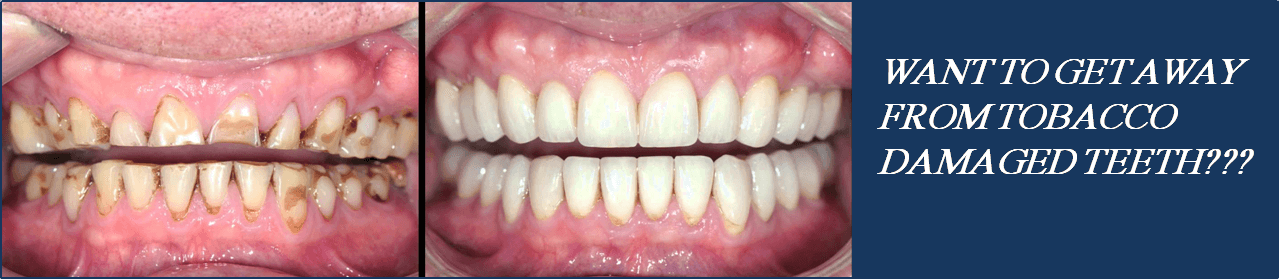

- Tobacco chewers whose teeth are reduced in height